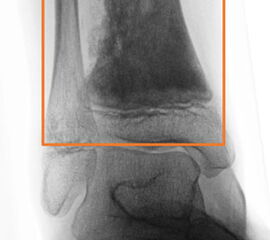

In unserem eigenen Patientengut werden alle gut- und bösartige Knochen- und Weichteil­tumoren des Fußes, einschließlich dem Bereich der distalen Metaphyse der Tibia und Fibula als Fußtumoren definiert. Die Metaphyse ist hierbei durch ein gleichseitiges Rechteck (Qua­drat) festgelegt (Abb. 5), das seine Basis am breitesten Teil der Wachstumsfuge hat (Ruedi, 2000). Explizit ausgeschlossen hiervon werden alle oben genannten Pseudotumoren.

Konventionelle Röntgenaufnahmen bleiben in der bildgebenden Diagnostik von Knochen­tumoren das wichtigste diagnostische Werkzeug. Zahlreiche Informationen können hierdurch einfach, kostengünstig und im Vergleich zu einigen alternativen Untersuchungsmethoden strahlungsarm eingeholt werden. Die in der konventionellen Diagnostik eruierbaren und zur weiteren Abklärung erforderlichen Informationen beinhalten Befunde zu Topographie der Läsion (Lokalisation im Fußskelett und im individuellen Knochenbereich), Begrenzungen der Knochenläsion, Art der Osteodestruktion und Periostreaktion, radiologische Erscheinung der Tumormatrix (Zusammensetzung des Tumorgewebes, z.B. dystrophe Verkalkungen) sowie Verhalten und Ausmaß der Weichteilbeteiligung. Dabei sollte der abzubildende Knochen immer einschließlich der benachbarten Strukturen und angrenzenden Gelenke dargestellt werden. Die Röntgenaufnahmen sind stets in mind. zwei Ebenen anzufertigen. In Abhängig­keit der Beschwerden sind belastete Aufnahmen im Stehen anzustreben um zusätzliche Aussagen zur Statik zu erlangen. Die Schrägaufnahme des Fußes stellt eine sinnvolle Ergänzung zu den Standardeinstellungen (dorsoplantar/a.p. und streng lateral) dar um die Knochen des Fußskeletts möglichst überlagerungsfrei darstellen zu können. Ziel- und Spezialaufnahmen können bei Bedarf zusätzlich durchgeführt werden.